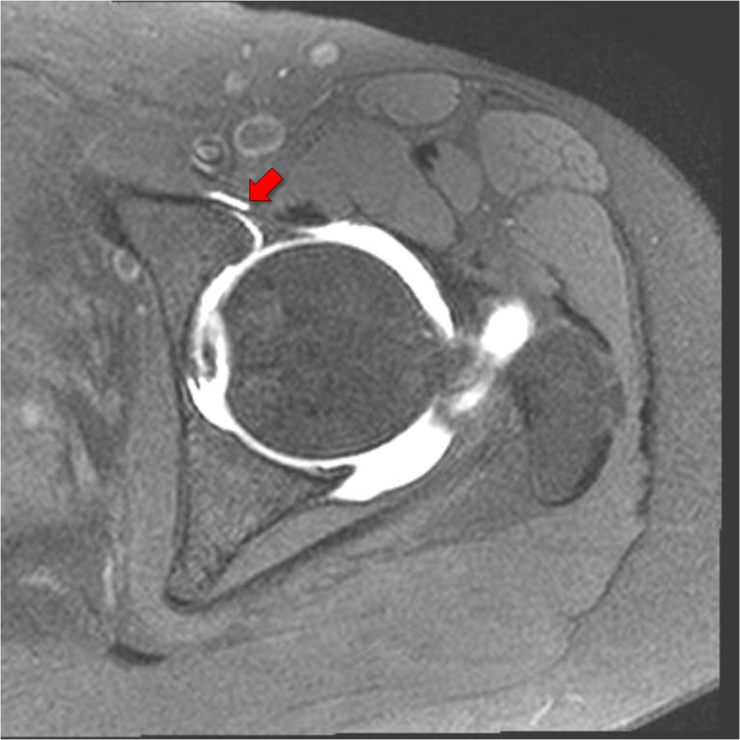

Q=어머니는 오랫동안 어깨를 앓고 있었지만, 얼마 전부터 잠자리에서도 어깨 통증에 시달리고 있습니다. 팔도 거두는 것이 큰일이라고 합니다. A=흔히 있는 어깨의 질환으로 충돌 증후군(회전 근개 손상)오십견(유착성 관절 피막염), 석회화 건염, 관절 와진 파열, 근막 통증 증후군 등이 있고 외에도 목과 어깨의 다양한 부위의 신경 압박으로 어깨의 통증이 있습니다. 많은 환자들이 이렇게 말하고 있습니다. “여러 병원·의원에서 뢴트겐(X선)을 찍고 이상이 없는 주사를 맞아 물리 치료를 했지만 별로 효과가 없어 그 때만 증세가 더 심해지는 것 같아요.”X선에서는 뼈 이외의 무수한 구조물을 볼 수 없습니다. 골절에 의한 어깨 통증 외에 엑스 레이로 보이는 어깨 통증의 원인은 골암와 석회화 건염 뿐입니다. 그러므로 외상이 없을 때는 X선 검사는 필요 없다고 생각합니다. 많은 분들이 장기간 충돌 증후군의 치열한 인대 손상을 주사와 물리 치료에만 의존했으나 수술 시기를 놓쳐서 심한 관절염으로 팔을 쓰지 못한다 아쉬운 경우를 자주 봅니다. 어깨의 회전통과 활막이 어깨 관절을 안정시키는 유일한 구조물입니다. 그래서, 인대 손상과 어깨의 회전통이 심한 위축이 오면 어깨 관절이 불안정해지면서 장기적으로 치열한 관절염에 진행되고 팔을 못쓰게 될 뿐 아니라, 아파서 잘 수 없게 됩니다. 진찰시에 충돌 증후군이 의심스러우면 꼭 자기 공명 영상(MRI)검사를 해야 합니다. MRI영상으로 힘줄 손상 정도로 근육의 퇴화 정도를 보며 수술 여부를 정합니다. 그래서 미국의 상당수 주에서 MRI검사 없이는 관절경 수술을 금지하고 있습니다. -영상 의학과 의원(소죠은데 원장)-

Q=어머니는 오랫동안 어깨를 다치셨지만, 얼마 전부터는 잠자리에서도 어깨 통증으로 고생하고 계십니다. 팔도 올리기 힘들대요. A=흔히 흔한 어깨질환으로 충돌증후군(회전근개손상), 오십견(유착성관절막염), 석회화건염, 관절와순파열, 근막통증후군 등이 있으며 이외에도 경추나 어깨 여러 부위의 신경압박에 의한 어깨통증이 있습니다. 많은 환자들이 이렇게 말합니다. 여러 병의원에서 엑스레이(X-ray)를 찍고 이상이 없어 주사를 맞고 물리치료를 했는데 별 효과가 없고 그때만 증상이 더 심해지는 것 같아요. 엑스레이에서는 뼈 이외의 무수한 구조물을 볼 수 없습니다. 골절에 의한 견통 외에도 엑스레이에서 볼 수 있는 견통의 원인은 골암과 석회화 건염뿐입니다. 그렇기 때문에 외상이 없을 때는 엑스레이 검사는 필요 없다고 생각합니다. 많은 분들이 장기간 충돌증후군으로 인한 극심한 인대 손상을 주사와 물리치료에만 의존하다가 수술 시기를 놓쳐 심한 관절염으로 팔을 사용할 수 없게 되는 안타까운 경우를 자주 봅니다. 어깨 회전근과 활막이 견관절을 안정시키는 유일한 구조물입니다. 따라서 인대 손상과 어깨 회전근의 심한 위축이 오게 되면 견관절이 불안정해지고 장기적으로 심한 관절염으로 진행되어 팔을 사용하지 못하게 될 뿐만 아니라 아프고 잠을 잘 수 없게 됩니다. 진찰 시 충돌증후군이 의심되면 반드시 자기공명영상장치(MRI) 검사를 해야 합니다. MRI 영상에서 힘줄 손상 정도와 근육 퇴화 정도를 보고 수술 여부를 결정합니다. 따라서 미국의 많은 주에서 MRI 검사 없이는 관절경이나 수술을 금지하고 있습니다. – 영상의학과의원(서정대원장)-